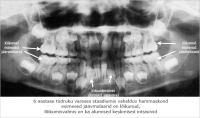

Klõpsa pildil, et avada ta printimiseks eraldi aknas (284x230)